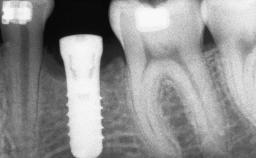

A 47-year-old woman who had suffered from aggressive periodontitis requiring a number of periodontal interventions over more than 10 years was referred by her general dental practitioner and periodontologist for bone augmentation and implant therapy. Her failing dentition had already been scheduled for extraction. The patient expressed a desire for implant-supported fixed restorations and esthetic improvement of her lower face. She had agreed to consult with a maxillofacial surgeon after the referring dentist had suggested bone augmentation. An initial examination by the maxillofacial surgeon revealed mobility of all residual teeth in a patient who was very unhappy with the function of her removable partial dentures. Due to periodontally migrated flaring teeth and loss of occlusal support, the vertical dimension of occlusion was dramatically reduced. The patient was displeased with her lower face because of deepened nasolabial, commissural, and supramental folds.

Bone Augmentation Horizontal|Sinus Floor Elevation|Staged|Vertical

Bone Volume Deficient vertically or deficient vertically AND horizontally